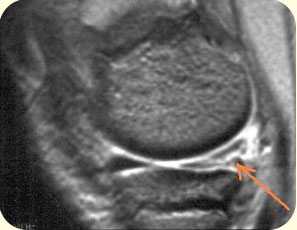

2. ЯМРТ (ядерно-магнитно-резонансная томография) Современный, высокоинформативный, безопасный метод исследования. Лучше всего подходит для определения мягкотканых повреждений: связочного аппарата, повреждений менисков, хряща и др.

разрыв крестообразных связок коленного сустава (изображение слева), разрыв заднего рога внутреннего мениска коленного сустава (изображение справа)